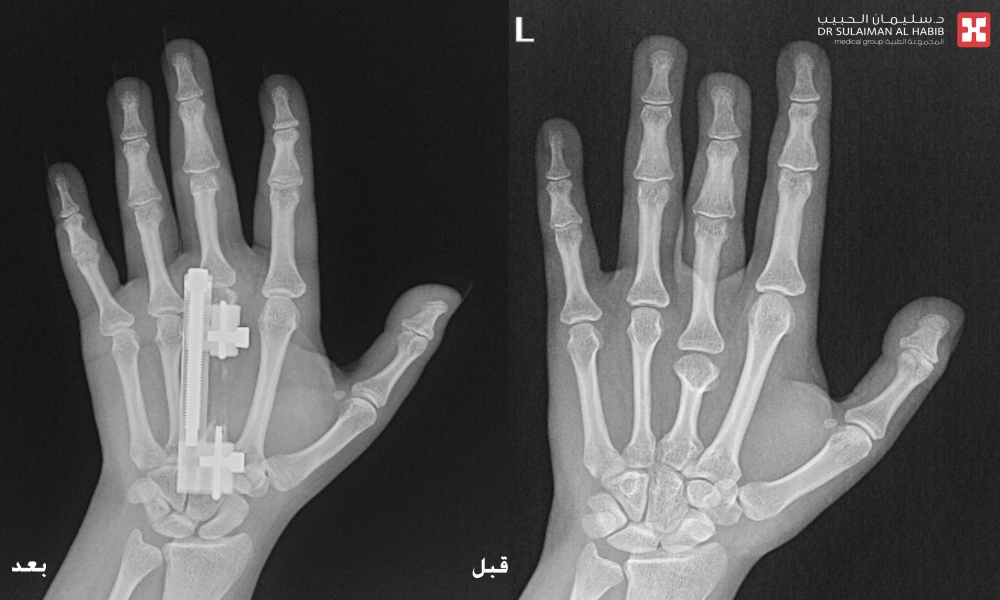

مشيراً إلى أن نتائج الفحوصات أوضحت وجود تشوه خلقي باليدين مع قصر بالإصبع الأوسط بأكثر من ٤ سم، بالإضافة إلى وجود ميلان وإنحسار بالحركه، وهو الأمر الذي أثر على الوظيفة الطبيعية لليد وبشكل كبير، فضلاً عن التأثير النفسي بسبب التشوه الظاهر. موضحاً أن الفريق الطبي المعالج قام بدراسة كافة النتائج، واضعاً خطة يتم فيها تطويل الإصابع.

وأوضح الدكتور الرفاعي أن العملية استغرقت ساعتين ونصف، وتم فيها استخدام تقنية التطويل والتعديل التدرجي بإستخدام جهاز Super Mini LRS ، والذي يتميز بسهولة الإستخدام، وصغر الحجم كي لا يتسبب في الإزعاج خاصة فترة الليل أو عند الحركة، نقلت بعدها المراجعة إلى جناح التنويم، للمتابعة الحثيثة، وعلى إثر تحسن حالتها خرجت من المستشفى بعد يومين وهي بصحة جيدة، مع وضع برنامج دوري لزيارة العيادة ومتابعة نتائج التطويل.

وأكد د. الرفاعي أن اليد أصبحت طبيعية تماماً من الناحية الوظيفية والشكلية ولله الحمد، مشيداً بتوفر الأجهزة والتقنيات المتقدمة لعلاج حالات التشوه العظمي، موضحاً أن حالة المراجعة، تُعد من الحالات النادره والمعقده، وذلك لوجود شبكات من الأوعية الدموية والأعصاب والأوتار المحيطة بمنطقة اليد، والتي تتطلب خبره عاليه ودقه بإجراء هذه الجراحات.